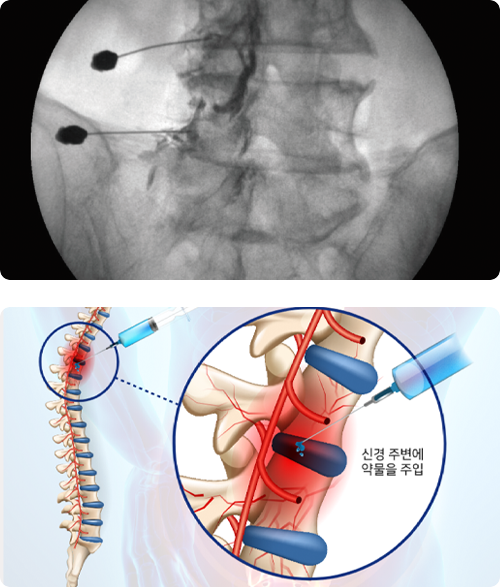

허리 협착증 최소 침습

신경차단술

추간판 탈출증 및 협착증으로 인한 심한 방사통을 일으키는 환자에게

효과적인 시술로 통증을 일으키는 척추 신경을 찾아 염증을 줄이는

약과 유착방지제 등을 투여하여 통증의 원인을 해결하는 치료법을 말합니다.

대부분의 경우 허리 통증은 비수술적으로 간단히 치료가 가능 합니다.